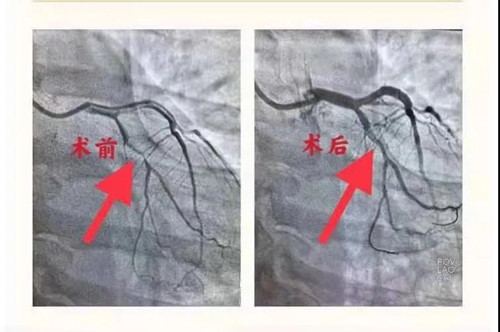

护士为患者静脉采血、建立静脉通道,作心理疏导,安慰患者焦虑情绪。通过一系列的术前准备工作,于当日晚上为患者行冠脉造影检查,结果显示回旋支近段狭窄约90%。重症医学科主任王秋艳、医生于红波为患者及家属详细讲解了病变情况,在支架和药物球囊方面介绍了各自的优缺点,详细的为患者制定了个体化治疗方案,患者及家属通过医生讲解,加强了治疗的信心,目光中充满了对医生的信任。重症医学科介入手术团队熟练的在原有病变充分扩张的基础上应用药物球囊介入治疗,治疗结束后患者胸痛症状立即缓解。